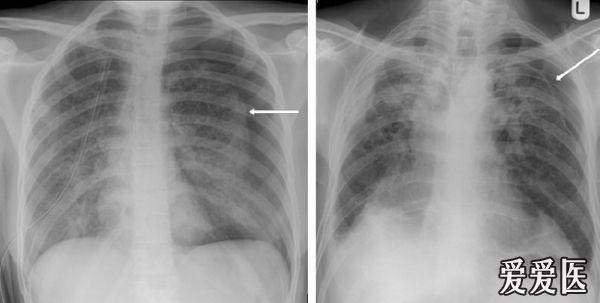

气胸影像图片,气胸胸片典型图片

呼吸版经验交流(7)气胸:影像学解读指南

关于气胸的x光片